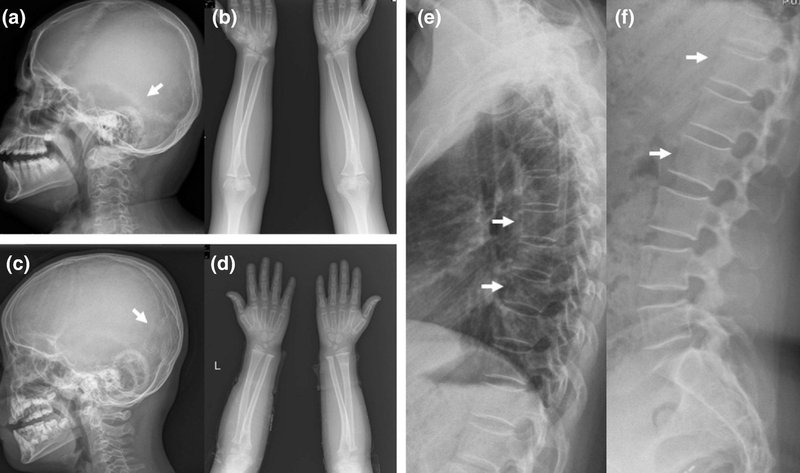

1994年にアメリカ・コネチカット州の男性が交通事故に遭っても、骨折ひとつしなかったので病院でX線撮影をしたところ、医師たちが驚愕することになりました。

同年代男性の「8倍」の密度を持っていたのです。

骨が異常に密すぎてX線がほとんど通らないほどでしたが、本人には痛み・障害・生活上の不便など一切なし。

この時点で医学界では前例がない“謎の超高密度骨”として話題に。

それから6年後、家族全員が同じように異常な骨密度を持つことがわかり、遺伝によって受け継がれた特異体質だったことが判明しました。

↑この骨が異常に密な状態を大理石骨病と呼ぶ。

しかし実際には、この状態がケガを減らすわけではない。むしろ、異常なほど密な骨はり脆い(ガラスと竹を比較すると…確かにガラスは密度が高いが、柔軟性が必要な場面では、それが強度に繋がるわけではない)。